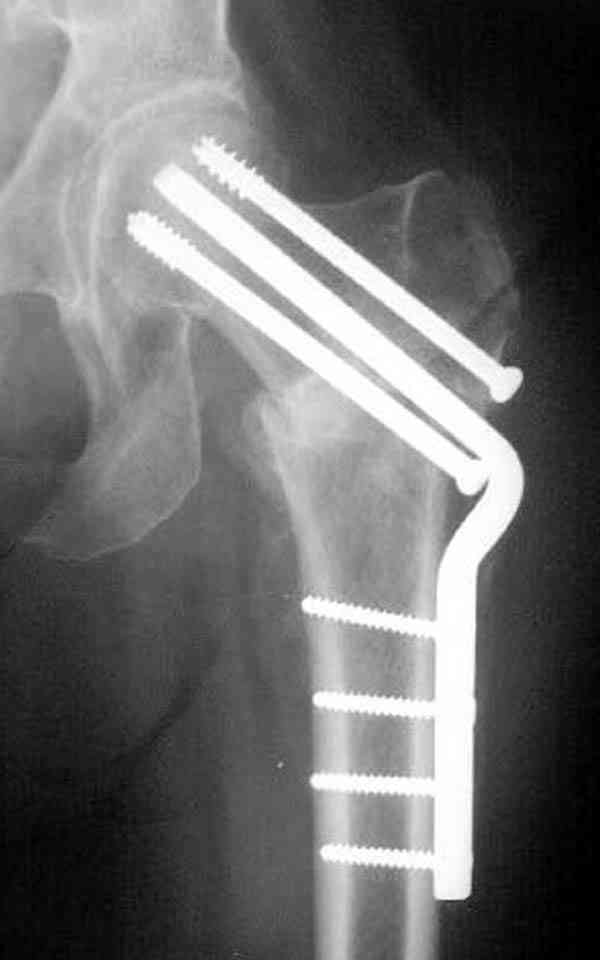

Здесь случай перелома из-за ослабления латерального кортекса через 3 недели после операции на шейке. Шурупы были установлены под большим углом, слабый латеральный кортекс не выдержал нагрузку.

Коллега Челноков прав, здесь еще имеется риск перелома за счет ослабления латерального кортекса. Во время установки канюлированных шурупов за редким исключением спица вводится с одного раза, множественные попытки ослабляют латеральный кортекс, что станет источником перелома в этом месте.

В идеале для профилактики рефрактуры шурупы надо вводить не больше, чем под 130 градусным углом и не ниже уровня малого вертела.

Насчет биомеханических преимуществ одного шурупа тоже возникает вопрос. Если придерживаться канонов механики, для перелома шейки необходимо 3 паралельных шурупа, расположенных ближе к кортикальному слою шейки.